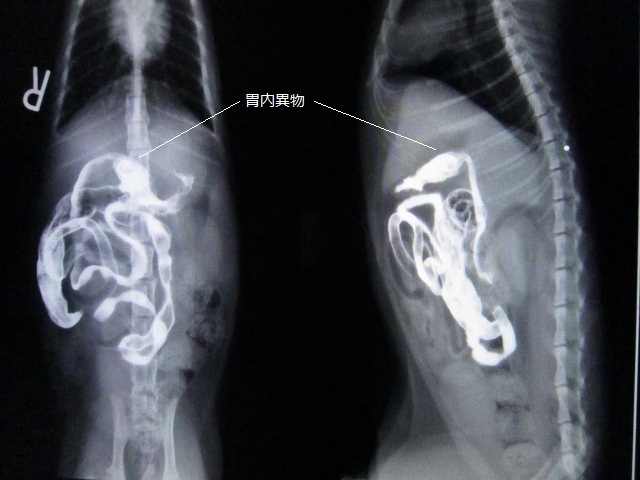

バリウム2時間後2

バリウム投与2時間後のレントゲンです。

ちょっと見えにくいですが、胃内に異物があります。